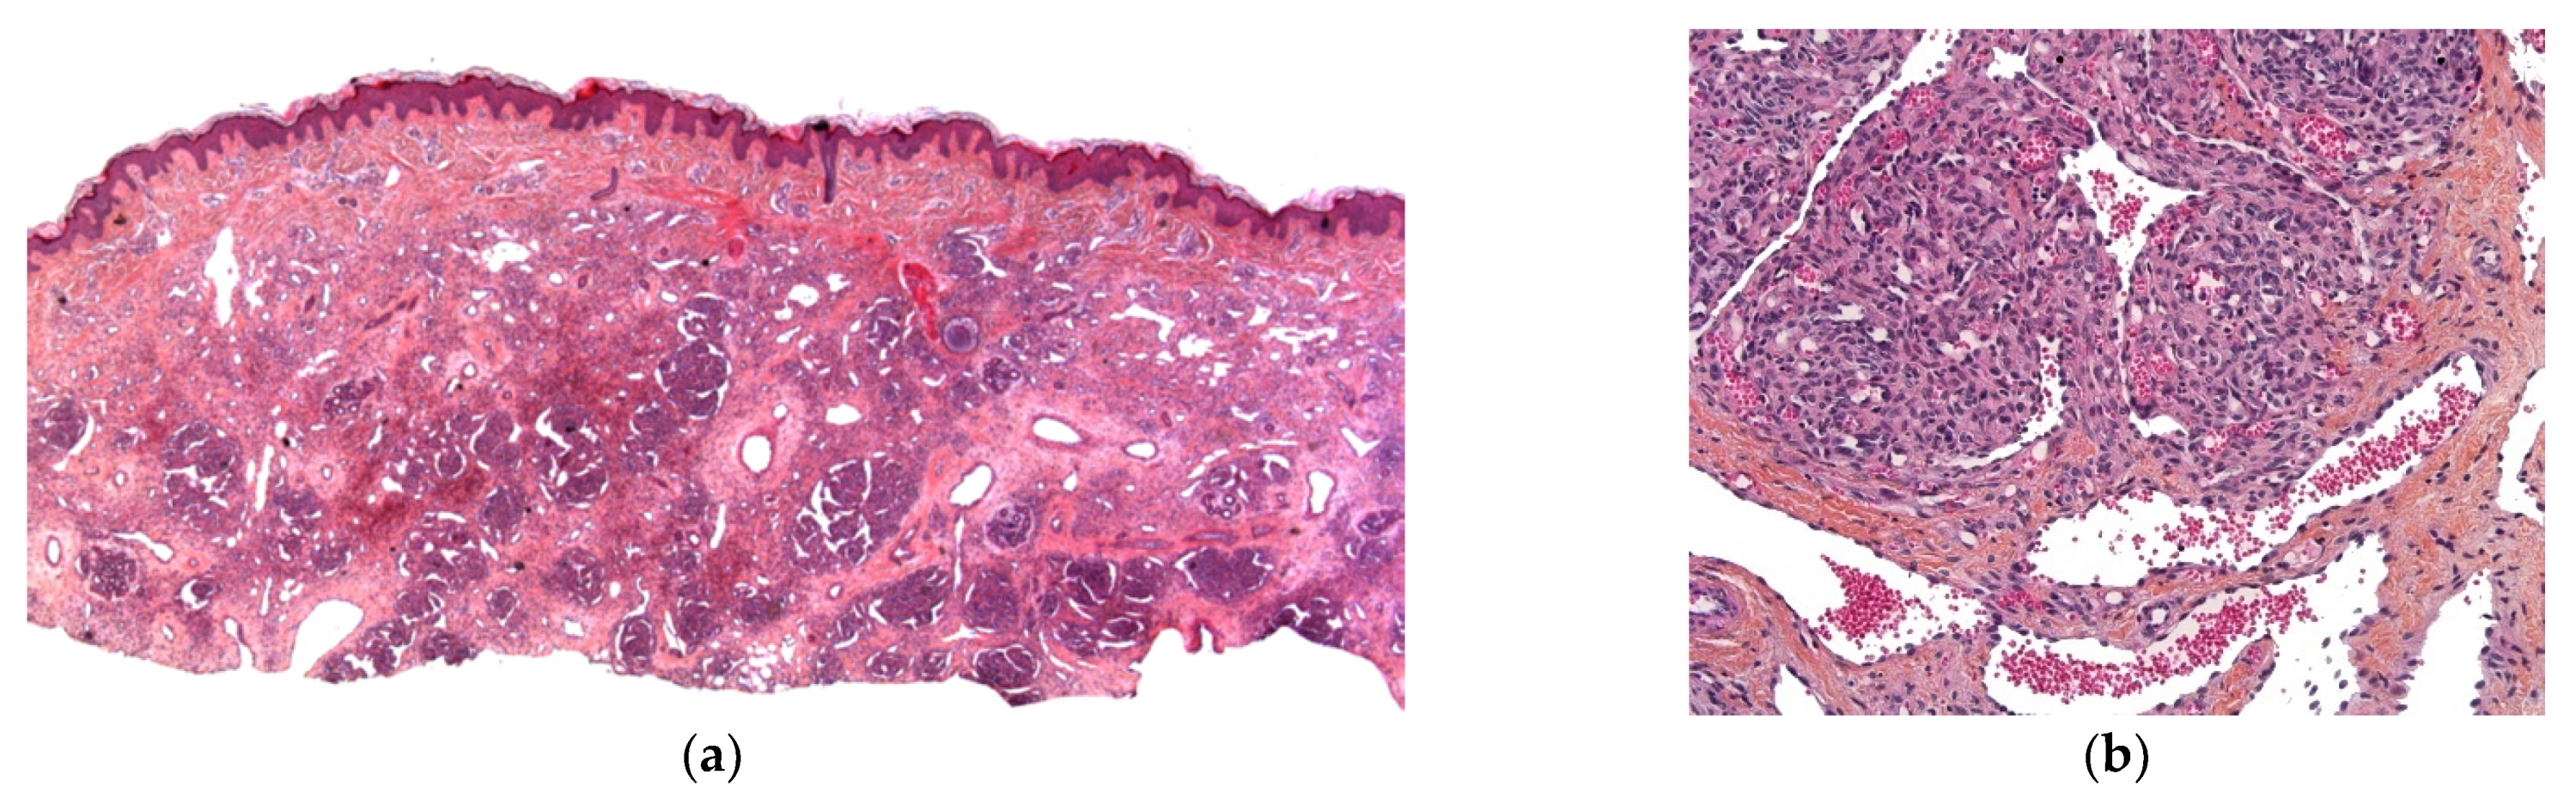

Figure 4.

Congenital leukemia cutis: (a) blueberry muffin rash; (b) 4× dense dermal infiltration separated from the epidermis by a grenz-zone; (c) 10× medium-sized blastic cells arranged in single-file between collagen bundles and with a peri-vascular and peri-adnexal arrangement as well; (d) 25× apoptotic cells and mitotic figures; (e) CD68 intense positivity; (f) Ki67 immunostaining: almost 100% of nuclei are positive.

Histology

In most cases, the diagnosis is straightforward. A dense dermal infiltrate is separated from the epidermis by a “grenz zone” and extends into the subcutaneous tissue with a peri-vascular and peri-appendageal arrangement. Cells are arranged in single file between the collagen bundles. They are medium-sized, with a high nuclear-cytoplasmic ratio, nuclear debris (apoptosis), and mitotic figures (Figure 4b–h). A good clue is the very high proportion of tumor cells, and almost no reactive inflammatory cells, in the infiltrate. CD68, lysozyme, and myeloperoxidase are the most sensitive immunohistochemical markers for detecting monoblasts (acute monocytic leukemia 5) or myelomonoblasts (acute monocytic leukemia 4), which account for the vast majority of leukemias at this age. In most cases, 90 to 100% of the cells are positive for KI67. Importantly, these immature monoblasts may lack CD163.